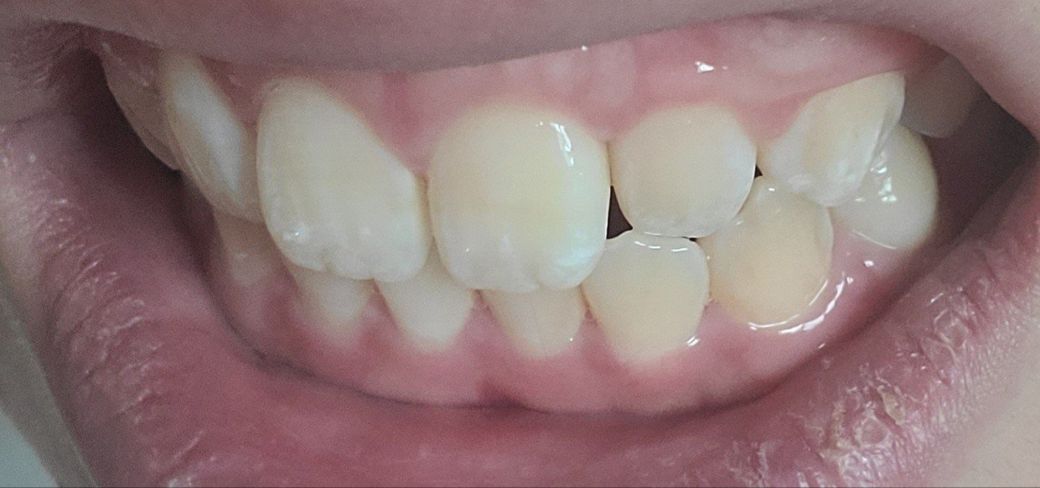

교정이 필요할까요?????????

송곳니랑 그부근 어금니가 좀 더 틀어져서 깊게?물려요 턱이 비대칭이있긴한데 이정도비대칭은 사람마다 있다고들 하는데

-한쪽 송곳니은 살짝 떠있고 반대쪽은 잘물려요

왜 그런건지 모르겠어요 중심선이 안 맞아서 그런 건가요?

앞니 옆쪽 치아하나도 위아래가 부딪힙니다

아래사진은 일부러 중심선맞춰서 찍은사진입니다

- 사진상으로 보면 크게 교정이 필요하실꺼 같진 않습니다. 만약 교정을 하게 되신다면 교정분석을 해봐야 전체 교정을 할지 부분교정을 할지 판단할수 있습니다.

-클리피씨와 인비절라인은 단순 비교할게 아니며, 케이스에 따라서 선택해야되야됩니다. 크게 치열에 문제가 없으셔서 인비절라인으로 하셔도 효과를 볼수 있을것같습니다.